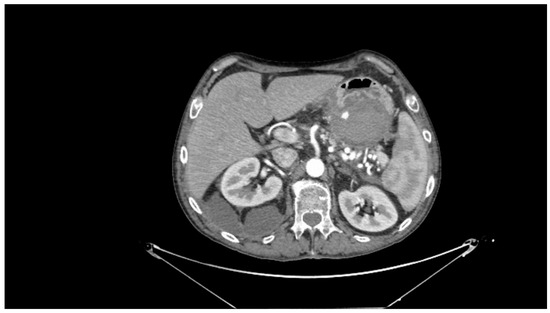

Contrast-enhanced CT scan remains a fundamental study for diagnosing complications of pancreatitis, including bleeding [31]. In cases of acute hemorrhagic pancreatitis, unenhanced CT typically shows significant enlargement of the pancreas with areas of low attenuation. After intravenous contrast administration, the pancreas displays irregular contrast enhancement, indicating areas of normal perfusion (i.e., viable parenchyma) and regions of reduced or abnormal perfusion (i.e., suggesting edema or necrosis) [21,31,39]. In cases of direct vascular damage or intraluminal bleeding, extravasation of contrast material can be seen, a highly specific finding for active bleeding (Figure 2) [31,40].

Figure 2. Contrast-enhanced abdominal computed tomography showing active bleeding inside a peripancreatic collection. Reproduced with permission from Bellio, G., et al. [29].